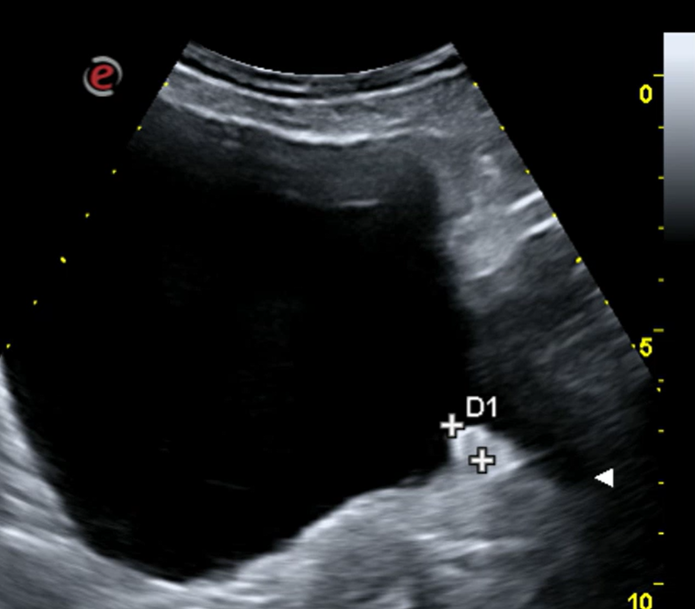

Ecografía renovescal realizada en consulta Atención Primaria: sin alteraciones salvo discreto engrosamiento en pared vesical posterior izquierda, de forma polipoide 9 x 9 mm, no captante de Doppler.

Orientación diagnóstica: sospechamos Tumor vesical.